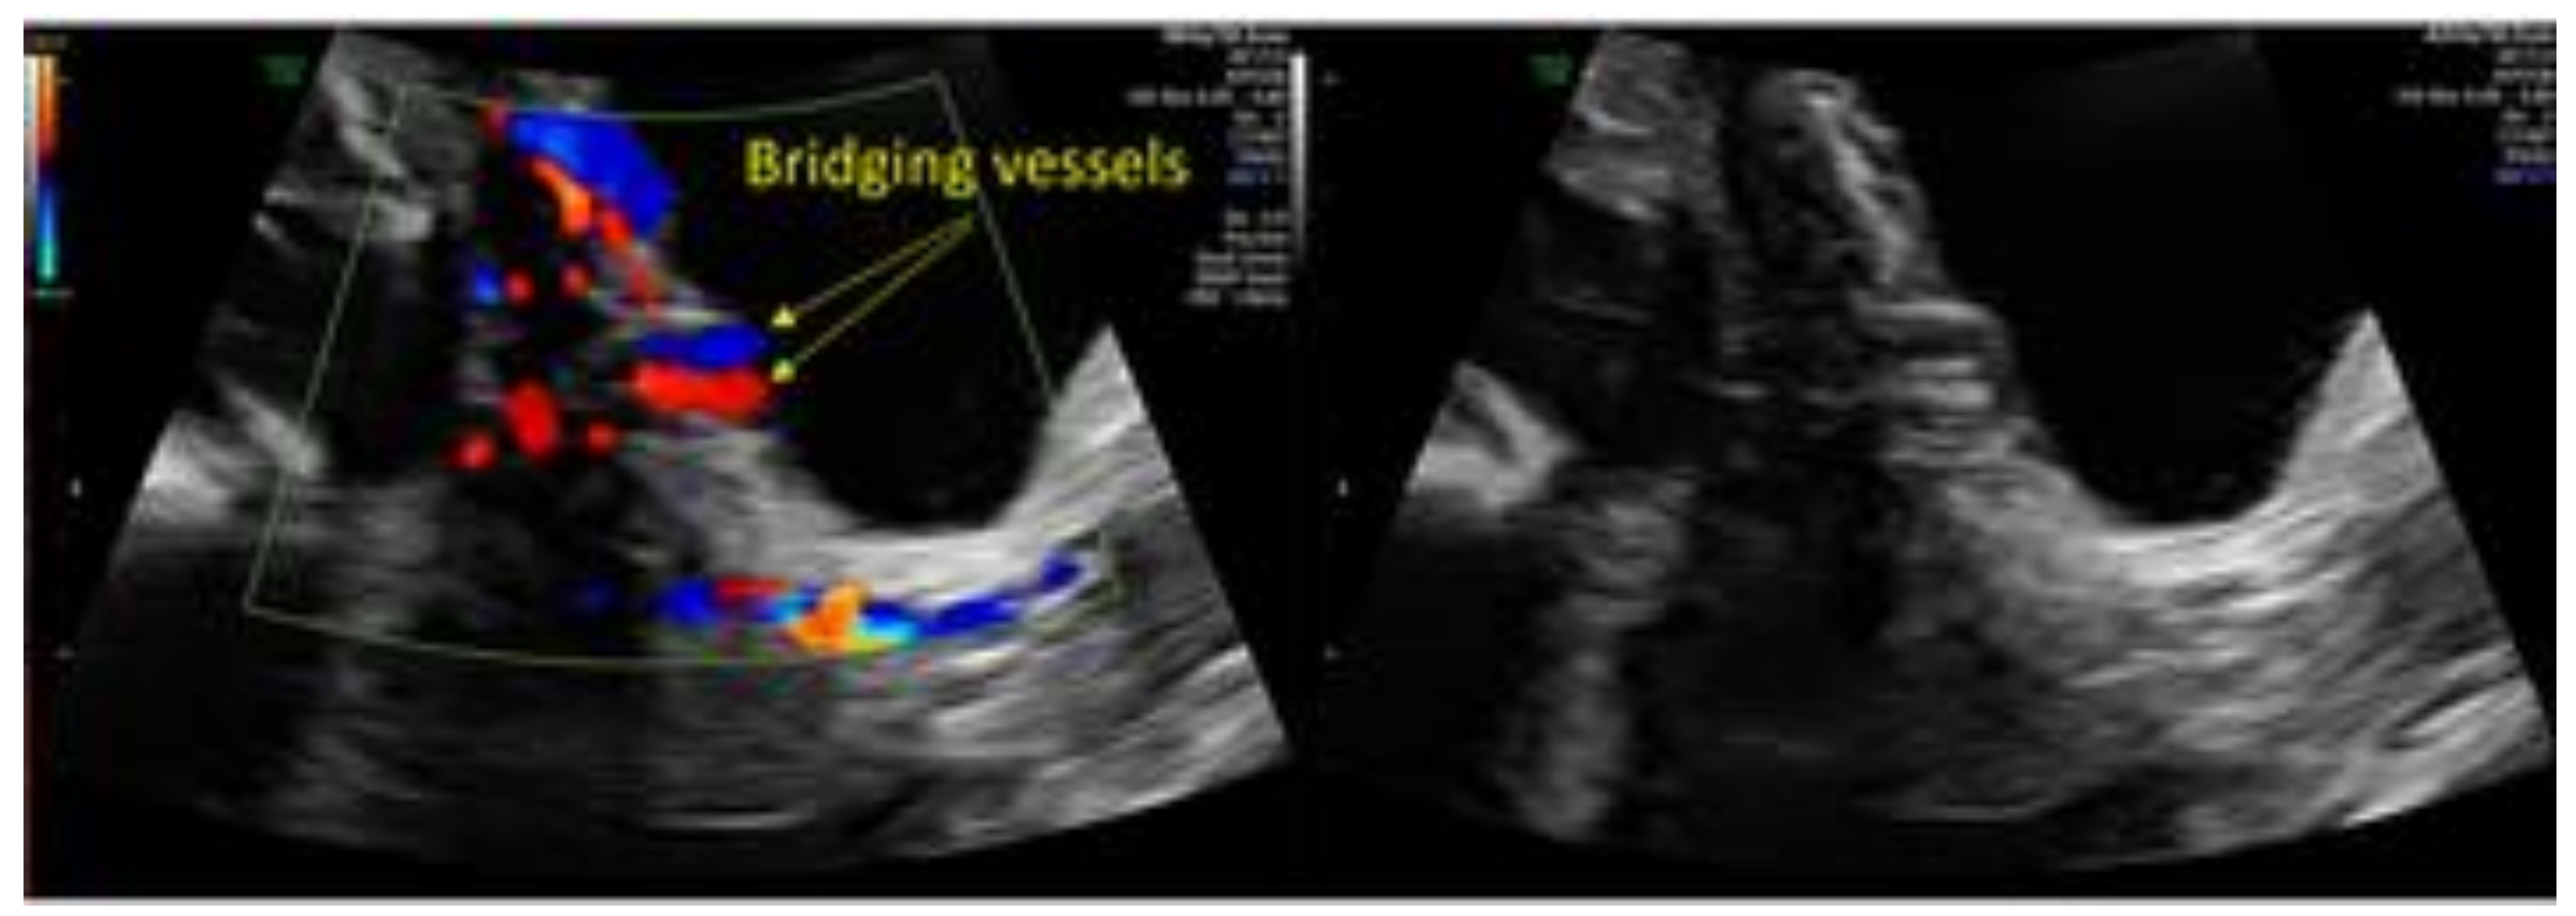

2. Case 1: History, Investigations, Treatment, and Outcomes

3. Case 2: History, Investigations, Treatment, and Outcomes

4.1. Diagnostic Comments